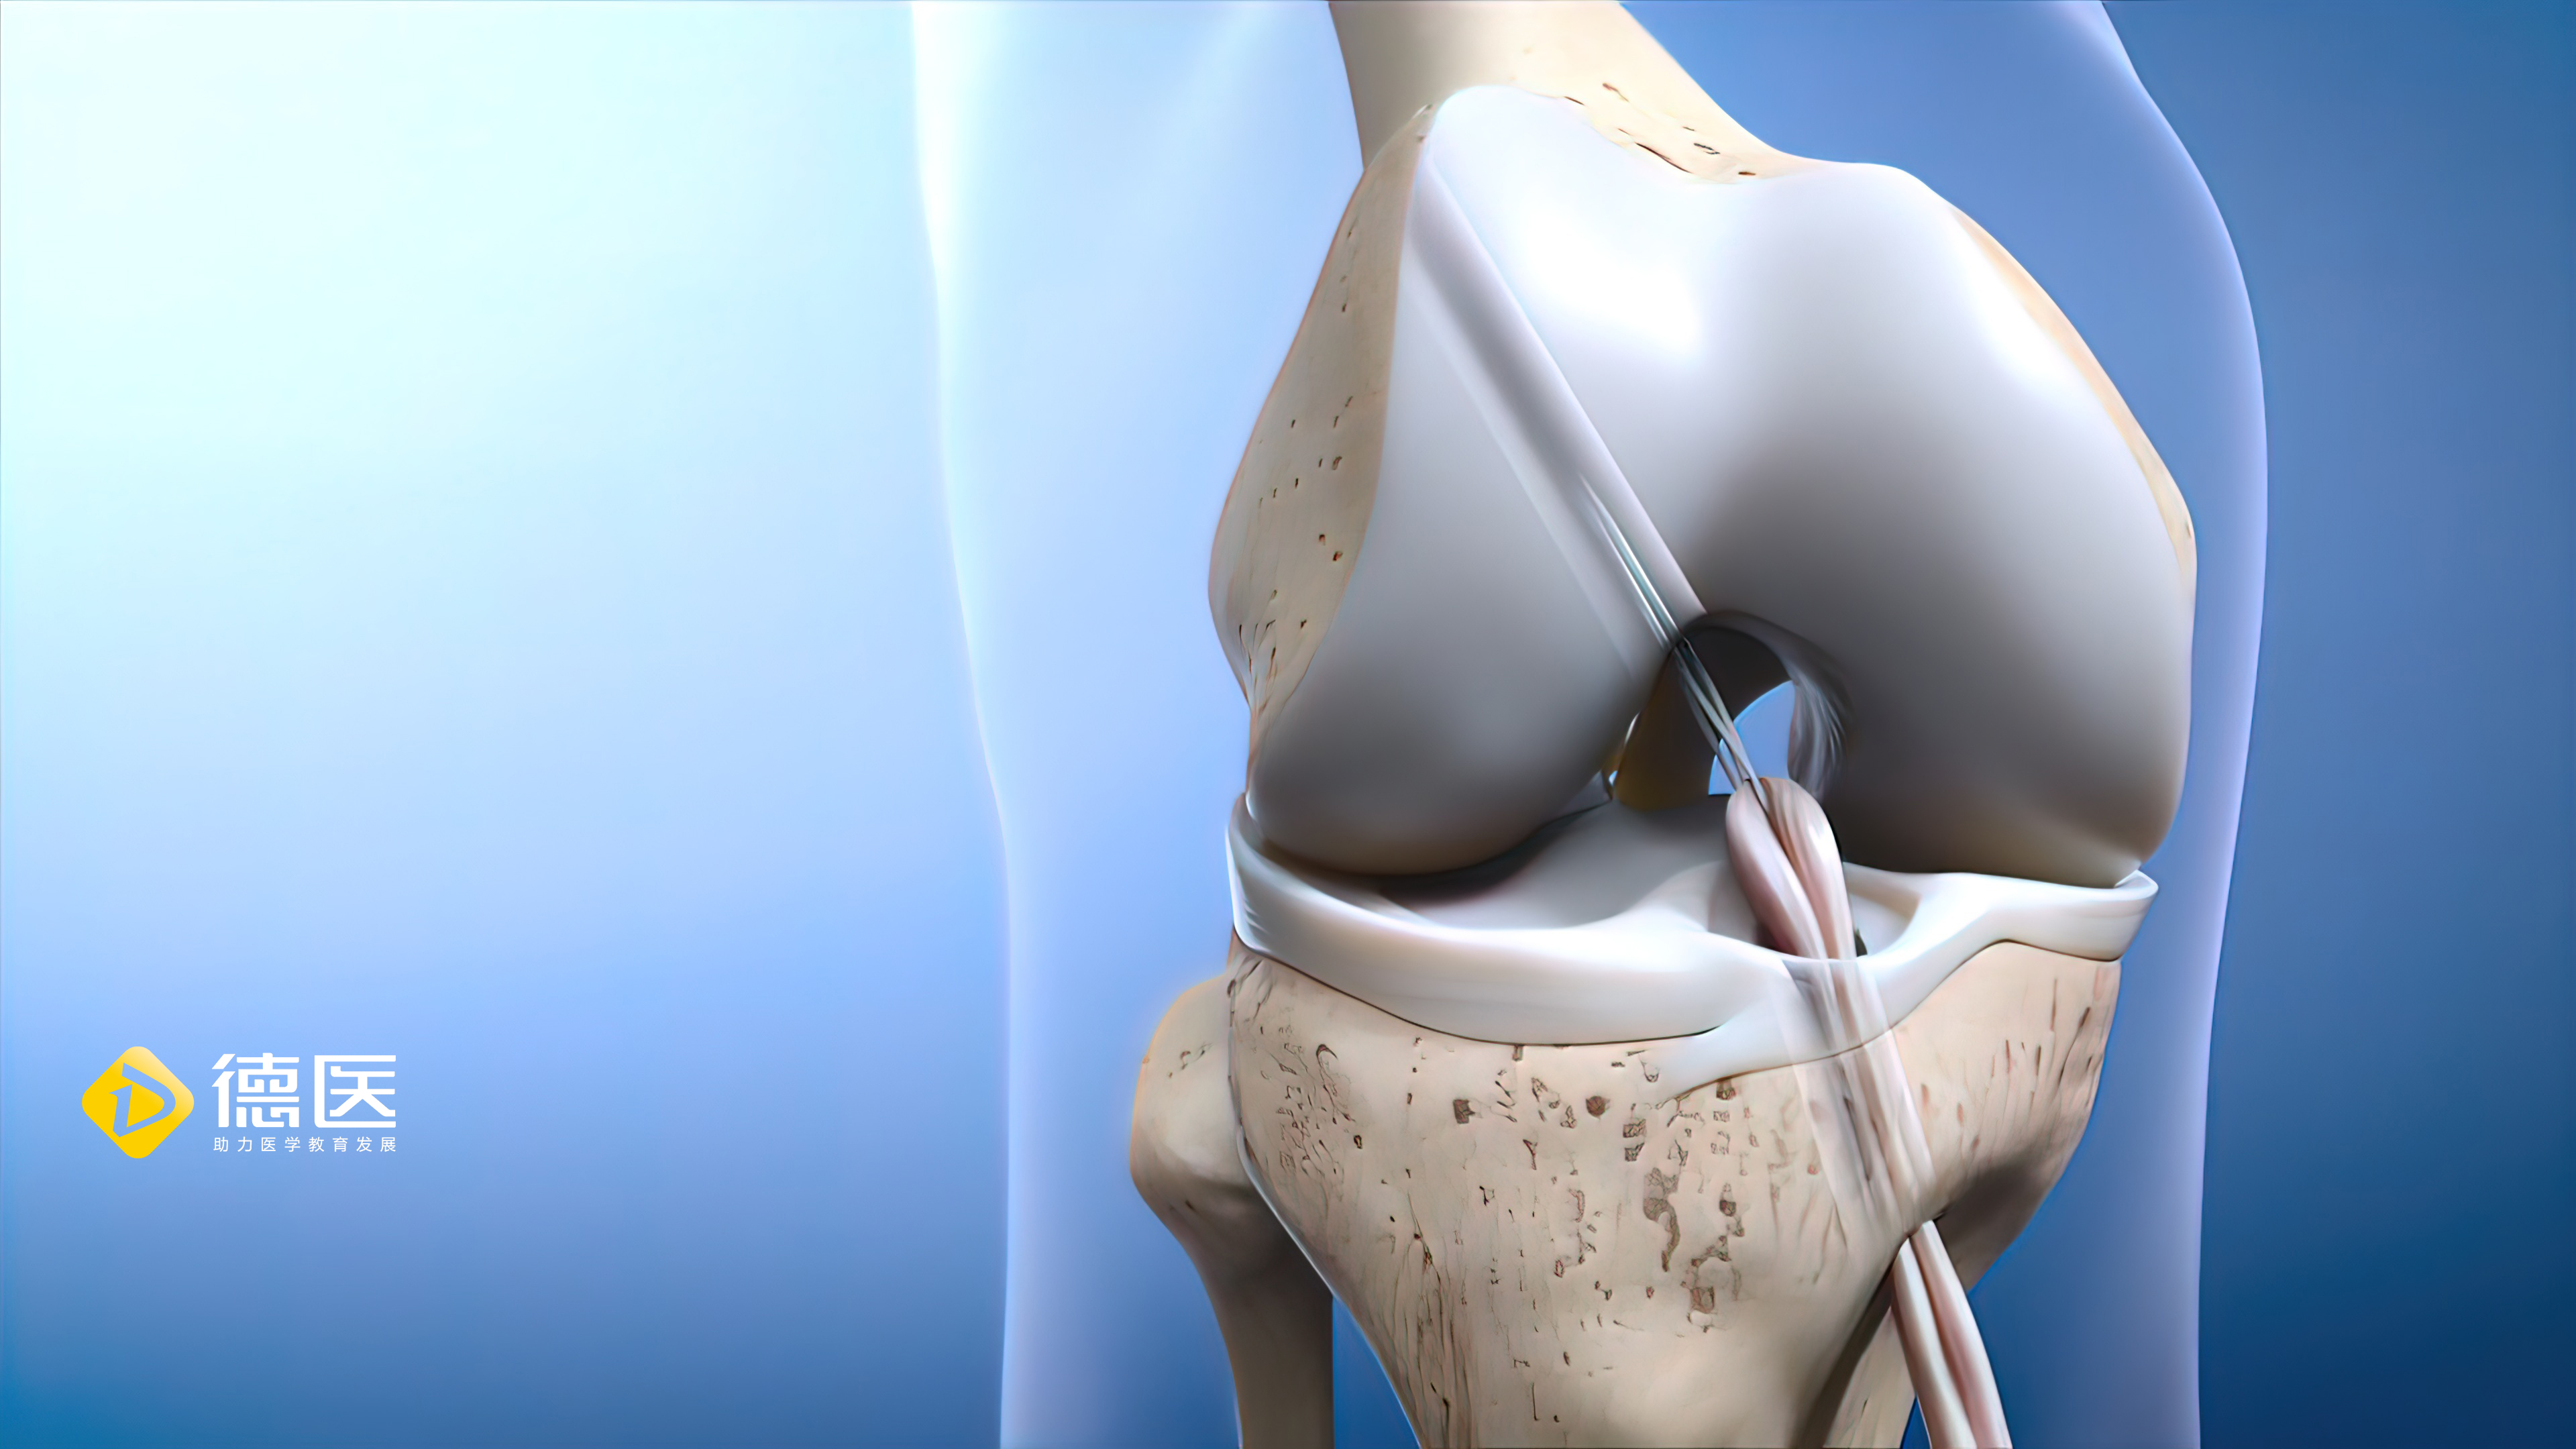

手把手教程:半月板中央化的操作技术要点!